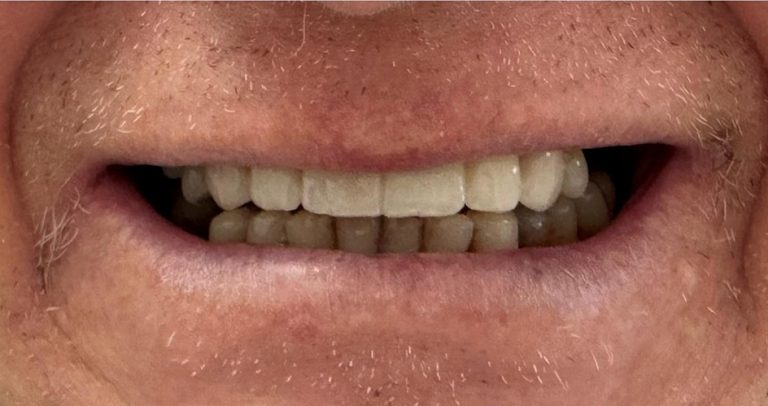

Résultat

Après